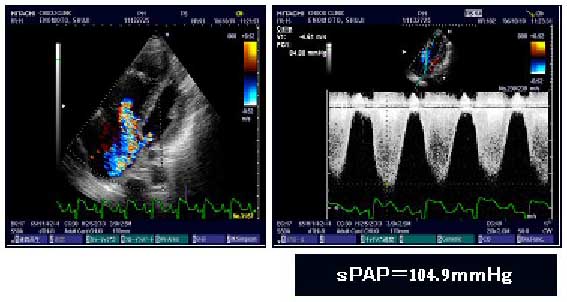

| 間質性肺疾患にみられる肺高血圧を見逃さないために ●間質性肺疾患と肺高血圧 間質性肺疾患は、呼吸器疾患の中では、決して頻度の多いものではありませんが、200種類にも及ぶ種々の疾患が含まれています。中でも、間質性肺炎、サルコイドーシス・過敏性肺臓炎などの肉芽腫形成性疾患は、代表的な間質性肺疾患です。間質という用語は、肺の解剖学的な部位を示すもので、ガス交換の場として重要な肺胞領域の間質とよばれる薄い血管やリンパ管、細胞外基質に富む場所を示しています。 肺胞間質に炎症細胞浸潤や、線維化がおこりガス交換機能が障害されて呼吸不全が起こってくる一連の疾患が間質性肺炎です。間質性肺炎には、急性、亜急性、慢性経過の疾患が含まれています。現在では原因不明の特発性間質性肺炎は7つの臨床画像病理型に分類されています。種々の並存する病態も含めた治療管理が問題となってくるのは慢性経過の間質性肺炎群(特発性肺線維症、線維化型非特異的間質性肺炎など)です。 間質性肺炎以外の間質性肺疾患の中でも線維化は起こります。過敏性肺臓炎は基本的に急性から亜急性発症を示しますが、慢性化した場合には、肺の線維化がみられ、慢性経過の間質性肺炎との鑑別が必要となります。サルコイドーシスでは、線維化は、間質性肺炎にみられる線維化とは異なった部位(気管支血管束周辺)に見られますが、慢性経過で呼吸不全や肺高血圧状態を引き起こすことがあります。 これらの慢性経過の疾患において肺高血圧の存在は、呼吸器科医師にもっと認識していただきたい問題です。従来、間質性肺炎を診断治療する呼吸器科医は、肺高血圧の存在をあまり視野にいれておらず、肺高血圧は、主に循環器医が診察しているということが多かったようです。しかし、間質性肺疾患、特に間質性肺炎の臨床においては、肺高血圧の存在は、きわめて重要な予後因子のひとつであり、肺高血圧の有無をいかに診断し、治療していくかは、呼吸器科医にとっても、忘れてはいけない大事なポイントです。 ●肺高血圧は、なぜ間質性肺疾患に合併してくるのか 肺動脈圧が上昇して右心系に負荷がかかってくる病態を肺高血圧といいます。肺動脈圧は正常では収縮期15~30mmHg,拡張期2~8mmHg、平均9~18mmHgとされています。肺動脈そのものを侵す原発性肺高血圧における診断基準にもとづいて、安静時平均圧25mmHg以上、収縮期圧35mmHg以上(または45mmHg以上)を肺高血圧ありと評価しています。 肺高血圧の分類としては、5つの型があります(表1)。間質性肺炎に伴う肺高血圧は3型として分類されています。線維化に伴う低酸素血症のために肺循環系の血管収縮が起こることと、線維化により肺血管系の量が減少すること、さらには、血管内における病理的変化により血管の閉塞機転などが合わさった病態の結果、肺高血圧が初期には労作時、進展した間質性肺炎例では安静時に認められます。膠原病に伴う肺高血圧は、間質性肺炎のない場合にも認められるために、肺高血圧分類では、1型に分類されています。血管内の病理的変化が強い場合には、間質性肺炎としての胸部写真上の陰影がなくても肺高血圧は認められます。さらに、慢性の肺血栓塞栓症により肺高血圧がおこる場合もあります。これは4型として分類されています。 サルコイドーシスでは、リンパ節腫脹により肺血管が圧排されて肺高血圧がおこる場合、肺の線維化による場合、さらには、血管内の閉塞病変venooclusiveによる場合などが考えられています。 ●肺高血圧の存在を見落とさないために 間質性肺炎も、肺高血圧も、一般に、慢性型の病態がほとんどです。急性間質性肺炎や亜急性間質性肺炎における肺高血圧の存在についての評価は実は不十分ではありますが、これらの頻度が少ないことと、急性期には、陰影の増加が見られ、これと症状所見とが平行していることが多いために、肺高血圧の評価は中心的な問題ではないのが実情です。 慢性型の間質性肺炎も、肺高血圧も、初期には、ほとんど自覚症状がありません。ある程度進行すると、労作時の息切れが自覚されます。間質性肺炎がある場合には、たいていの場合、労作時の息切れの増加は間質性肺炎の悪化と理解して治療されているのが現実です。しかし、労作時息切れの悪化が、胸部画像上の陰影の悪化や肺機能上の悪化の程度と一致しない場合には、いくつかの可能性があげられます。ステロイド治療中の場合には、ステロイド筋症による呼吸筋力の低下により息切れが悪化することがあります。気管支系の閉塞が合併しているために息切れ感が強まる場合もあります。二次性肺高血圧の存在による息切れの悪化は、放置したり、治療方針を間違うと右心不全をおこしてしまう場合もあります。二次性肺高血圧の可能性を見落とさないことは、経過予後にかかわる点で重要です。 ●二次性肺高血圧の可能性を見落とさないための診察ポイント 診察時に、息切れの増加、脈拍の増加、パルスオキシメーターでの酸素飽和度の低下(労作時と安静時)、胸部写真の経過での右心陰影の変化(右房拡大、肺血管陰影の増強など)と間質性陰影の変化の比較評価、肺機能検査での経時的変化(%VC、%TLC、FEV1/FVC、%DLCO)の評価(特に、%DLCOの低下)、心臓超音波検査による評価、血液中のKL-6、SPD、LDHの変化とhBNPの変化の比較などを中心に、現在の労作時息切れの増強が、間質性肺炎の悪化によるものか、肺高血圧によるものかの鑑別を行うことは重要です。 ●肺高血圧の診断における心臓超音波検査法の有用性 肺高血圧の診断と重症度の評価を正確に行うためには、右心カテーテル検査が必要です。この方法では、肺動脈圧や心拍出量を直接測定することができます。安静時の平均肺動脈圧値mPAPを測定し、これが25mmHgを超えている場合に肺高血圧ありと評価します。しかし、この方法は、入院を必要とし、侵襲的な検査であるので、繰り返しの検査は簡単にはできません。 心臓超音波検査は、侵襲の少ないもので、検査のための時間も20分くらいあればひととおりの測定ができますし、繰り返して行うことができ、経過の評価を外来においても可能とさせてくれます。 心臓超音波検査により、右室拡大、左室扁平化などの所見から右心負荷の存在を評価できます。ドプラ心臓超音波検査によれば、肺動脈圧をある程度正確に推定することができます。心臓超音波検査により得られる推定収縮期肺動脈圧値sPAPを指標とすると、40mmHg以上を軽度、50mmHg以上を中等度の肺高血圧と評価します。実際の肺高血圧の状態よりも高値を示す場合と低値を示す場合とがあることが、この検査方法における問題とされていますが、スクリーニング、あるいは経過観察においては、有用であると考えています。 さらには、心臓超音波検査を安静時のみならず、労作負荷時において行うことで、労作時の肺高血圧の程度を評価できますので、間質性肺炎に伴う肺高血圧の評価にとっては重要なポイントであります。安静時に比べると、推定肺動脈圧が平均14mmHg上昇するとの報告がありますから、安静時の値で肺高血圧がなくても、労作時には肺高血圧が見られるということになります。日常生活を考えると、間質性肺炎症例では、肺高血圧が労作時におこっている可能性が容易に示唆されるものです。労作時の肺高血圧の程度の評価は、専門外来でもまだルーチンには行われていないのが実情ではありますが、安静時の値から、常に、労作負荷時の値を推定しておくことが重要です。 ●心臓超音波検査とは 原理:超音波が生体を通過する際の性状によって反射する程度が異なることを利用し、反射波を検出し画像化したものです。検査法としましては、大きく断層法とドプラ法に分かれ、断層法は、壁運動や心拡大の評価、駆出率の評価に応用できます。またドプラ法はカラー、パルス、連続波、組織などがあり、血管内や心腔内の血流速度や心筋の運動速度を測定することにより心機能の評価に応用できます。 ●ドプラ法を用いた方法:三尖弁逆流から右室圧(肺動脈圧)を推定 ①左室短軸面あるいは心尖部四腔断面を描出してカラードップラ法を用いて三尖弁逆流を描出します。 ②カラードプラガイド下で連続波ドプラ法を用いて、三尖弁逆流ジェットの最大速度(VTR)を計測し、簡易ベルヌーイ式から右室―右房間の収縮期圧較差を求めます。 ③得られた値に右房圧5~20mmHg(一般的には10mmHg)を加えることにより右室圧が推定されます。右室圧は肺動脈狭窄や右室流出路の閉鎖がなければ収縮期肺動脈圧と等しいことから推定収縮期肺動脈圧(sPAP)としています。 図1:高度例 心尖部四腔断面で右室は著明な拡大を認め、短軸面では左室の扁平化が認められます。またカラードプラでは三尖弁逆流ジェットが高度に認められ、逆流の最大速度も4.61m/secと上昇し、推定収縮期肺動脈圧は104.9mmHgと高度な肺高血圧が推定されます。 ●間質性肺炎、サルコイドーシスにおける肺高血圧の頻度 中央診療所間質性肺疾患専門外来においては、2台のドプラ心臓超音波検査装置(日立製作所 ARIETTA 70、60)を用いて、間質性肺炎、膠原病肺、サルコイドーシスなどのスクリーニングと、経過観察、治療効果の判定などに活用しています。 ●二次性肺高血圧の臨床経過と治療管理法 二次性肺高血圧の検出は、膠原病性肺高血圧の一部を除いては、間質性肺炎症例の場合には、間質性肺炎の進行期であることが多いのではないかと思います。特発性肺線維症では、肺高血圧の存在は、予後不良因子であることが報告されていますし、われわれの成績でも、特発性肺線維症の肺高血圧存在例は生存期間が、存在していない症例に比較して明らかに短いことを示すことができます(図2)。いわゆる肺高血圧を示唆する所見(第二音肺動脈成分の亢進、肺動脈駆出音、胸部写真上の心胸比拡大など)が明らかになった時期からの治療では、予後を変えることは困難ではないかとおもいます。 われわれは、長期経過観察の中で、間質性肺炎の治療、肺高血圧の治療、種々の合併症の評価、を3つの軸として、薬剤の選択、在宅酸素療法の選択を考慮しています。なるべく自宅で通院治療を行うことを目標として、専門外来での評価を徹底させるようにしています。進展した患者さんでは、対象療法としての薬物治療、酸素療法をさらに徹底させて、QOLの維持を目標としています。 肺高血圧の治療としては、➀いたずらにステロイド薬を増量しない、➁免疫抑制薬についても増量しない、➂肺血管拡張薬のファーストチョイスとしては、アドシルカ(タダラフィル)、オプスミット(マシテンタン)に利尿剤を併用して導入しています。➃在宅酸素療法を導入するなどを中心にしています。 |